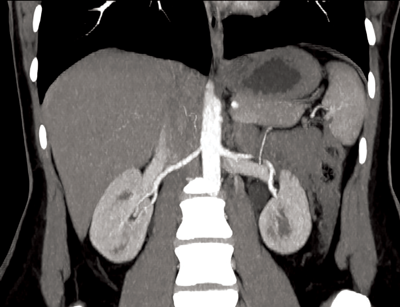

Figure 1: Coronal CTA demonstrating single renal artery supplying

each kidney and single vein draining each kidney.

Normal renal vascular anatomy (Figure 1)

Approximately 70% of the population have single bilateral renal arteries, originating from the abdominal aorta, at the superior margin of the second lumbar vertebral body, slightly below the superior mesenteric artery (SMA) origin [3]. The right renal artery orifice is located on the anterolateral wall of the aorta. The left renal artery originates slightly more inferolaterally than the right [2]. The typical dimensions of the renal arteries are 4-6cm in length and 5-6mm in diameter.

The renal arteries have slightly different trajectories, although both pass posteriorly towards the renal hilum. The right renal artery courses downward, and passes behind the IVC, while the left renal artery courses more horizontally and slightly upwards, posterior to the left renal vein. In the majority of cases the inferior adrenal arteries arise from the main renal arteries, and from the proximal aspect in two thirds of patients [2]. The main renal artery divides into segmental arteries approaching the renal hilum. The first division is typically the posterior branch, which passes posterior to the renal pelvis, to supply the posterior portion of the kidney. The remaining main renal artery then continues before dividing into four anterior branches at the medial aspect of the renal hilum: the apical, upper, middle, and lower anterior segmental arteries [4].There is no collateral arterial circulation between the renal segments; each of the segments is supplied by its own segmental artery [1]. Therefore segmental renal infarction will occur in the case of accidental segmental artery ligation.

Renal veins course anterior to the renal arteries. The segmental veins converge to form the main renal vein at the renal hilum [2]. The left renal vein usually receives the left adrenal, gonadal and lumbar veins before passing between the aorta anteriorly and superior mesenteric artery posteriorly, to enter the IVC. The shorter right renal vein, has no tributaries and enters the IVC at the level of first lumbar vertebra [3]. The right renal vein averages 2-4cm in length. The left renal vein averages 6-10cm in length [4]. In contrast to the segmental arteries there is free anastomosis of the venous system in the kidneys. This allows for ligation of the venous branches if a vessel is damaged during surgery, permitting an alternative venous drainage [1].